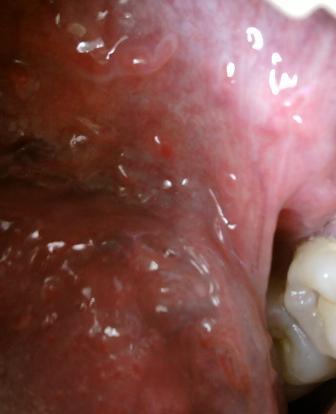

石家庄九州皮肤病医院 > 尖锐湿疣 > > > 石家庄哪家医院治疗尖锐湿疣比较权威对于尖锐湿疣顽疾的诊治,一定要引起重视,毕竟初期才是疾病诊治的最佳时期,希望大家应该能了解这一点,相信医学,经过正规的诊治,疾病才能够更加顺利的得以治愈。